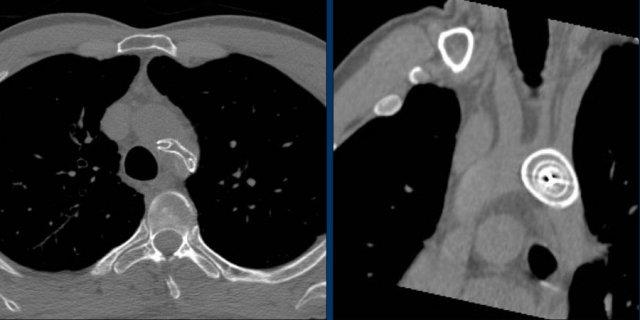

Bệnh nhân này có tĩnh mạch chủ trên bên trái tồn tại dai dẳng (LVCS).

Đây là một dị tật bẩm sinh hiếm gặp, có thể được phát hiện tại thời điểm đặt điện cực thiết bị tim.

Tĩnh mạch chủ trên bên trái tồn tại thông với nhĩ phải qua xoang vành.

Việc đặt điện cực thiết bị tim qua đường tĩnh mạch qua tĩnh mạch chủ trên bên trái tồn tại có thể gặp nhiều khó khăn về mặt kỹ thuật và trong một số trường hợp không thể thực hiện được.